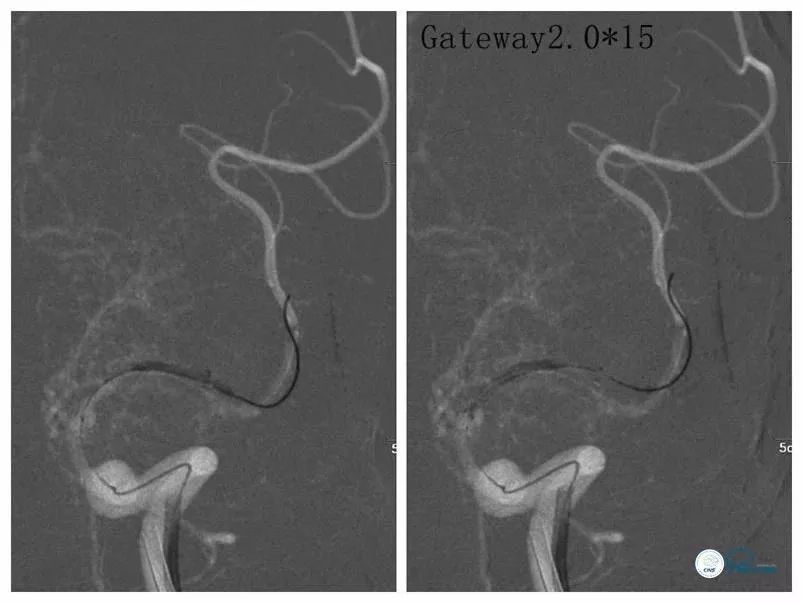

交换Transend微导丝(0.014”,300cm),送入Gateway球囊(2.0mm×15mm)扩张狭窄段(图9)。

图9